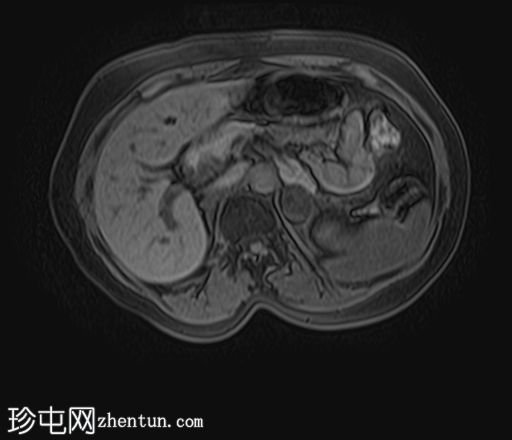

MRI

轴位T1加权像

(同相/反相)

轴位

T1加权像

脂肪抑制像

左侧肾上腺可见一边界清晰的病灶,大小约为3.0 × 2.4 × 2.0 cm。

化学位移成像显示,反相图像的信号强度较同相图像明显降低,与细胞内脂质含量相符。

右肾先天性缺失。左肾轻度肥大,信号强度正常。

肾上腺腺瘤的典型表现,反相成像可见明显的信号丢失。